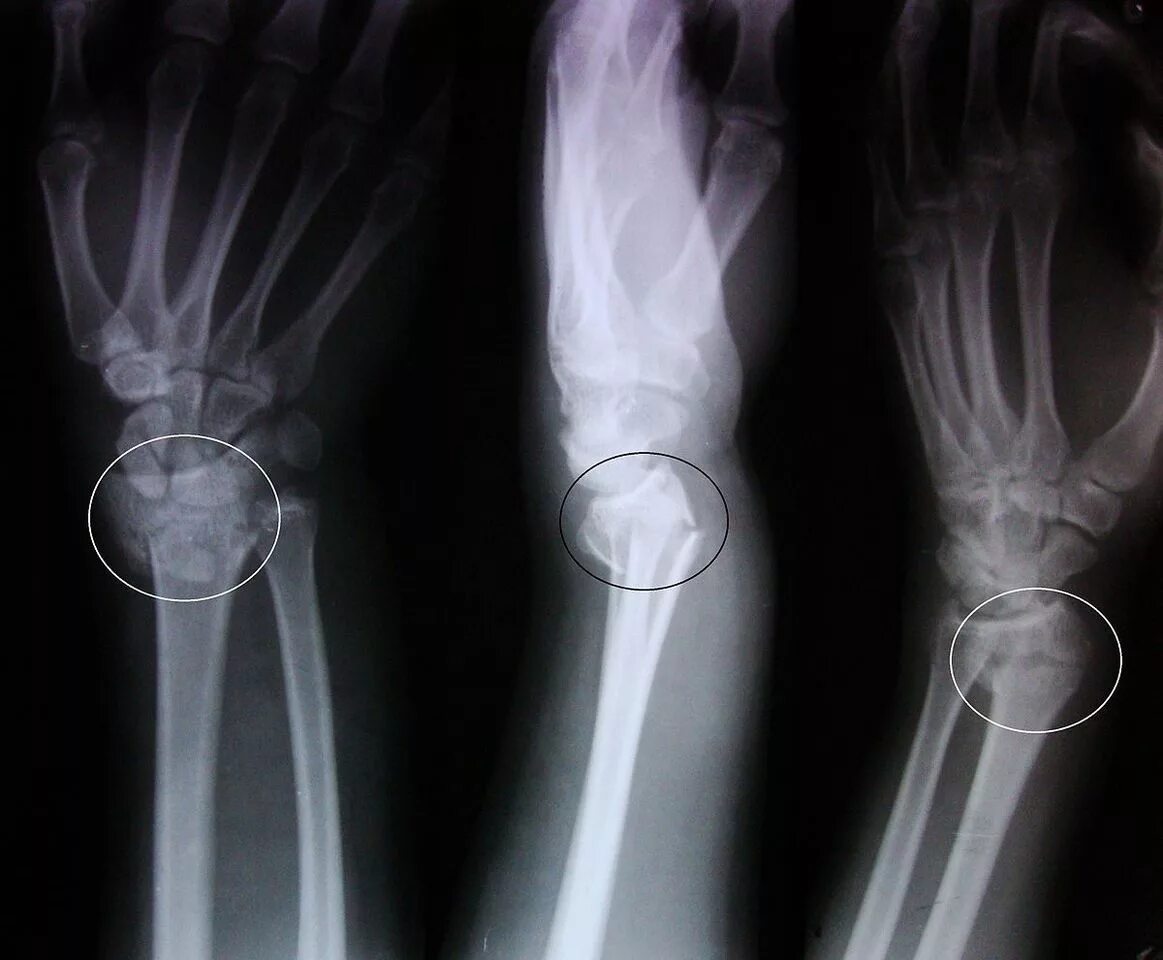

Заросший перелом со смещением